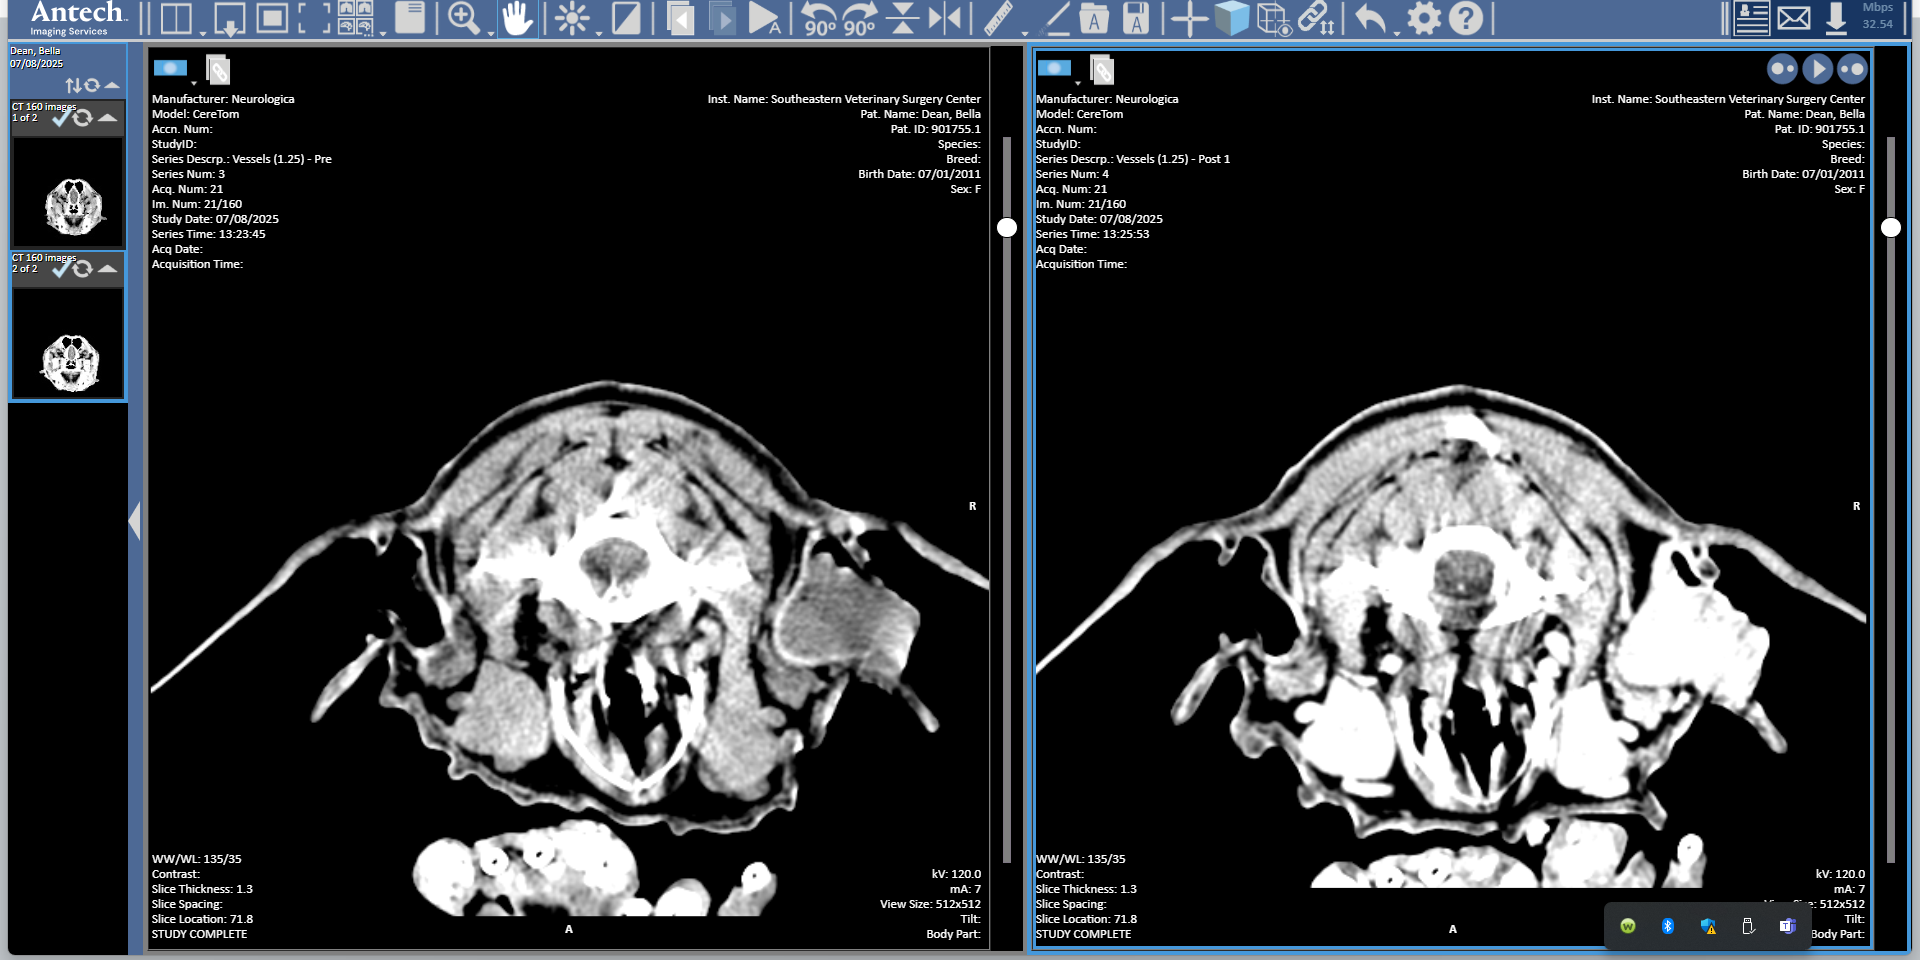

Bella is a 14 yr old Spayed Basset Hound Mix who presented to SEVSC for a melanoma involving the right ear canal. The melanoma was successfully removed with a total ear canal ablation of the right ear canal.